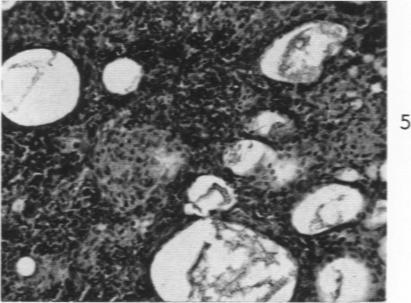

Studies on the mechanism of altered susceptibility to experimental allergic encephalomyelitis.

Am J Pathol. 1961 Oct;39(4):419-41.